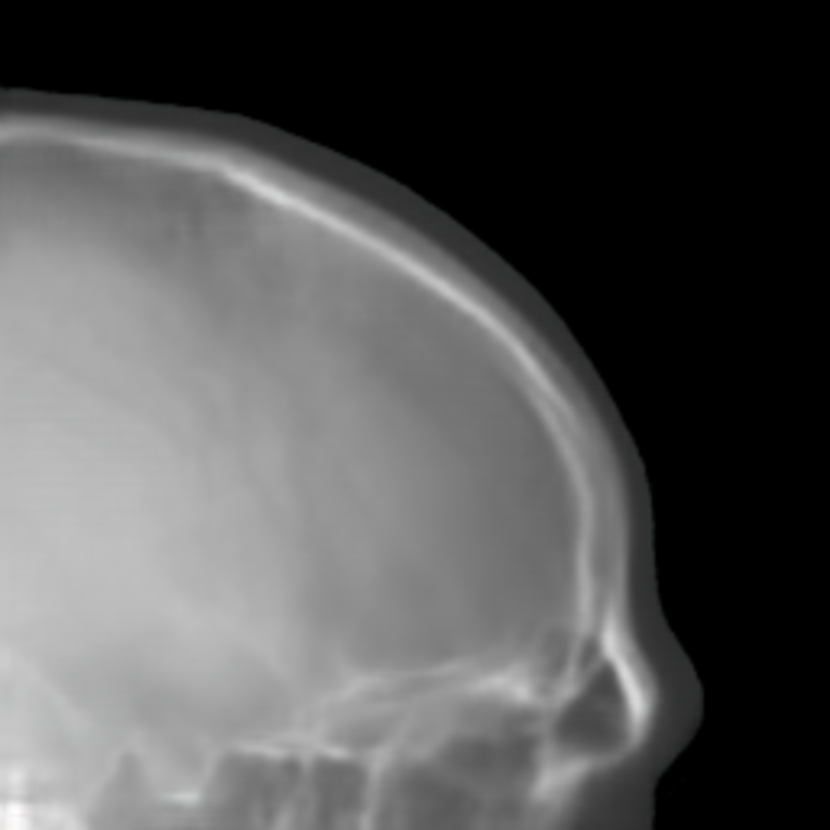

Refer to caption

(a) 10.02

(b) 5.43

(c) 4.67

(d) 5.43

(e) 4.92

(f) 4.07

Fig. 14: SR results on synthesized cephalogram from 3D volumes. The position of the example ROI patches in the bottom row is marked in (a). The perceptual indices of the top images are displayed in the corresponding subcaptions.

The SR techniques are also applied to synthetic cephalograms. The results of one Type I synthetic cephalogram example are displayed in Fig. 14. To visualize details better, an ROI patch is chosen for each method, whose position is marked in Fig. 14(a). Consistent with the results on the ISBI test patches, the patches of ESRGANRDB and ESRGANRRDB using LR patches as the input also suffer from checkerboard artifacts in Figs. 14(h) and (j). In addition, some undesired bright/dark artifacts occur in Fig. 14(j). In Figs. 14(i) and (k), apparent jagging artifacts are no longer observed for ESRGANRDB and ESRGANRRDB using ILR patches as the input, since the edges in the bicubic interpolation patches are smooth without jaggies. As expected, the patch predicted by pix2pixGAN has realistic appearance without the introduction of jagging nor checkerboard artifacts. Due to its superior performance to ESRGANRDB and ESRGANRRDB using ILR on the ISBI test patches, in this work we choose pix2pixGAN as the SR method.